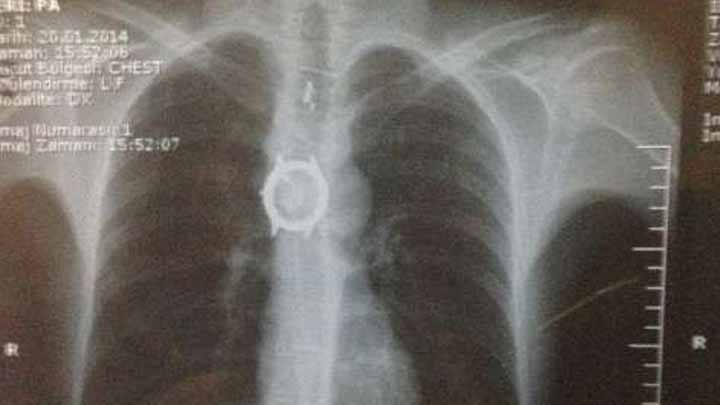

Türkiyədən bir kişinin mədəsindən əməliyyatla 6 cism çıxarılıb.

"Axar.az" xəbər verir ki, Van şəhərində Ərhan Özbilir adlı bir kişi mədəsindəki rahatsızlığa görə xəstəxanaya müayinəyə gedib.

Həkimlər gördüklərindən təəccübləniblər. Çünki xəstənin mədəsində qol saatı və oyuncaq ayı kimi əşyalar olub.

Vəziyyəti ağır olan xəstə əməliyyat edilib. Əməliyyatla Ozbilirin mədəsindən ümumilikdə 6 müxtəlif cism çıxarılıb.

Həkimlər bildirib ki, hazırda xəstənin vəziyyəti yaxşıdır.

Məlumata görə, Ərhan Özbilir psixoloji gərginlik keçirdiyi üçün həmin cismləri udub.